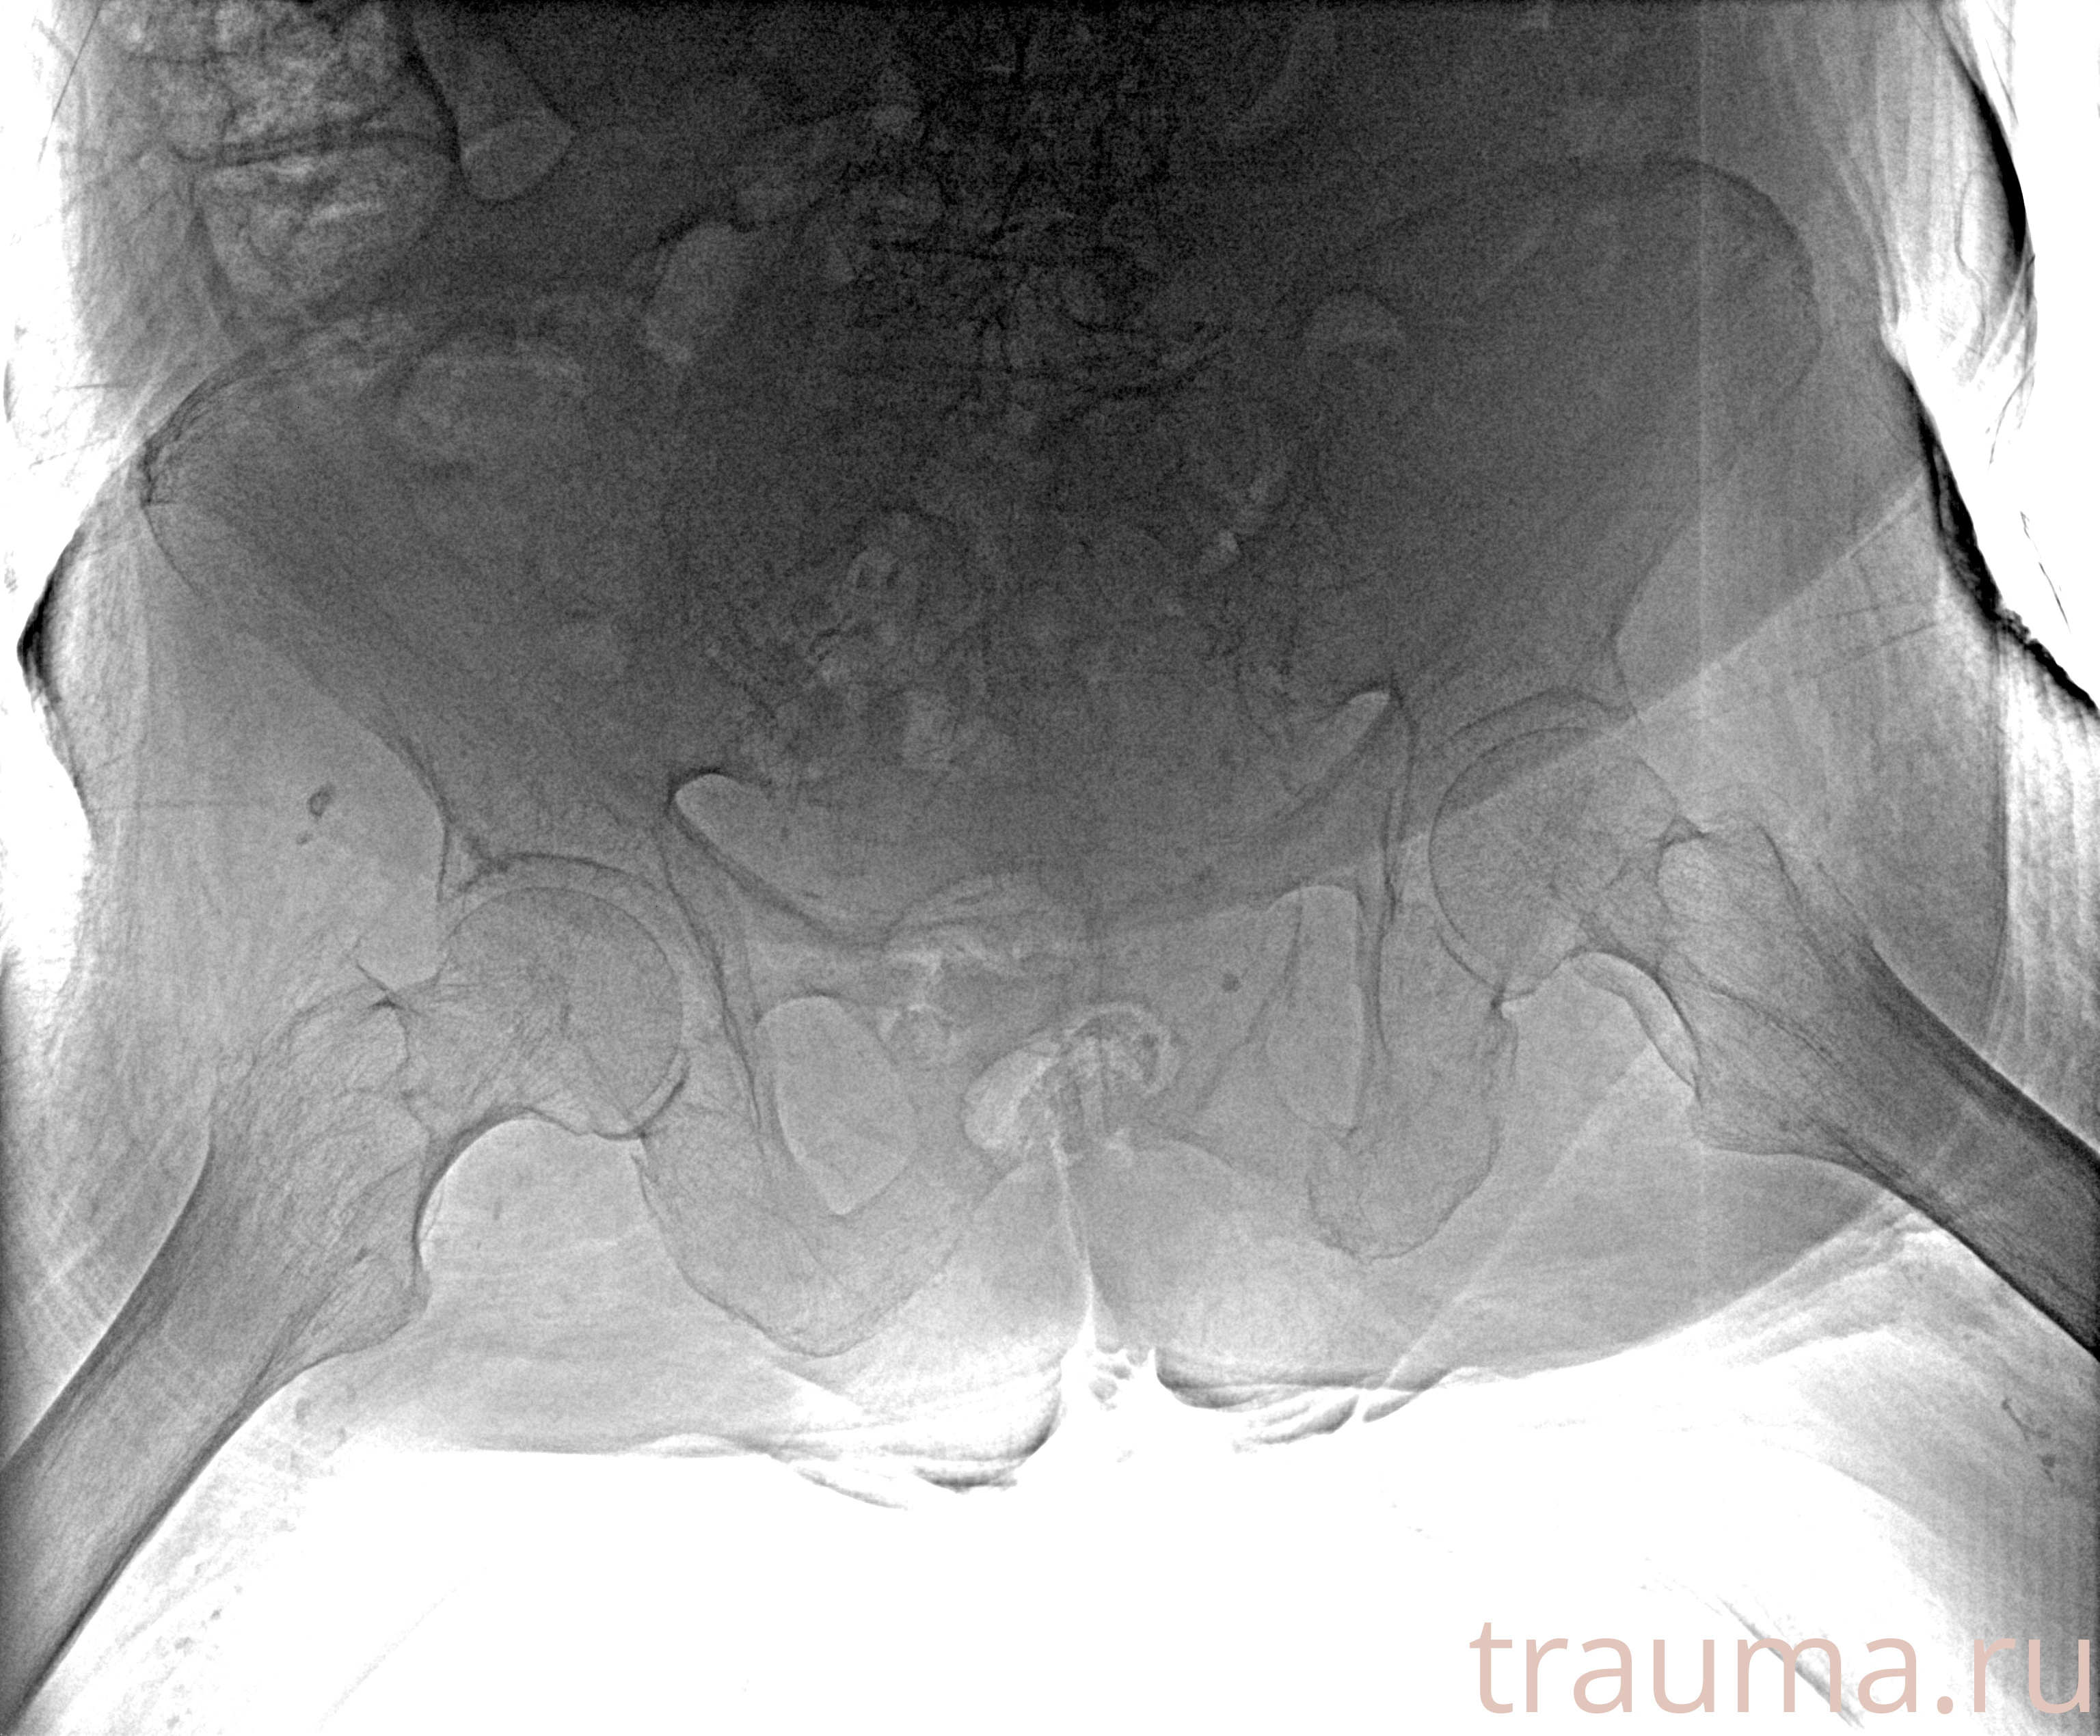

Рентгенограммы

Рентген на дому: по вашему адресу приезжает врач-рентгенолог, травматолог-ортопед с мобильным рентгеновским аппаратом, проводит диагностику травмы или заболевания, делает необходимые рентгенограммы, дает рекомендации по дальнейшему лечению. Получить качественные снимки в домашних условиях возможно благодаря уникальной методике, разработанной МосРентген Центром для института  Склифосовского